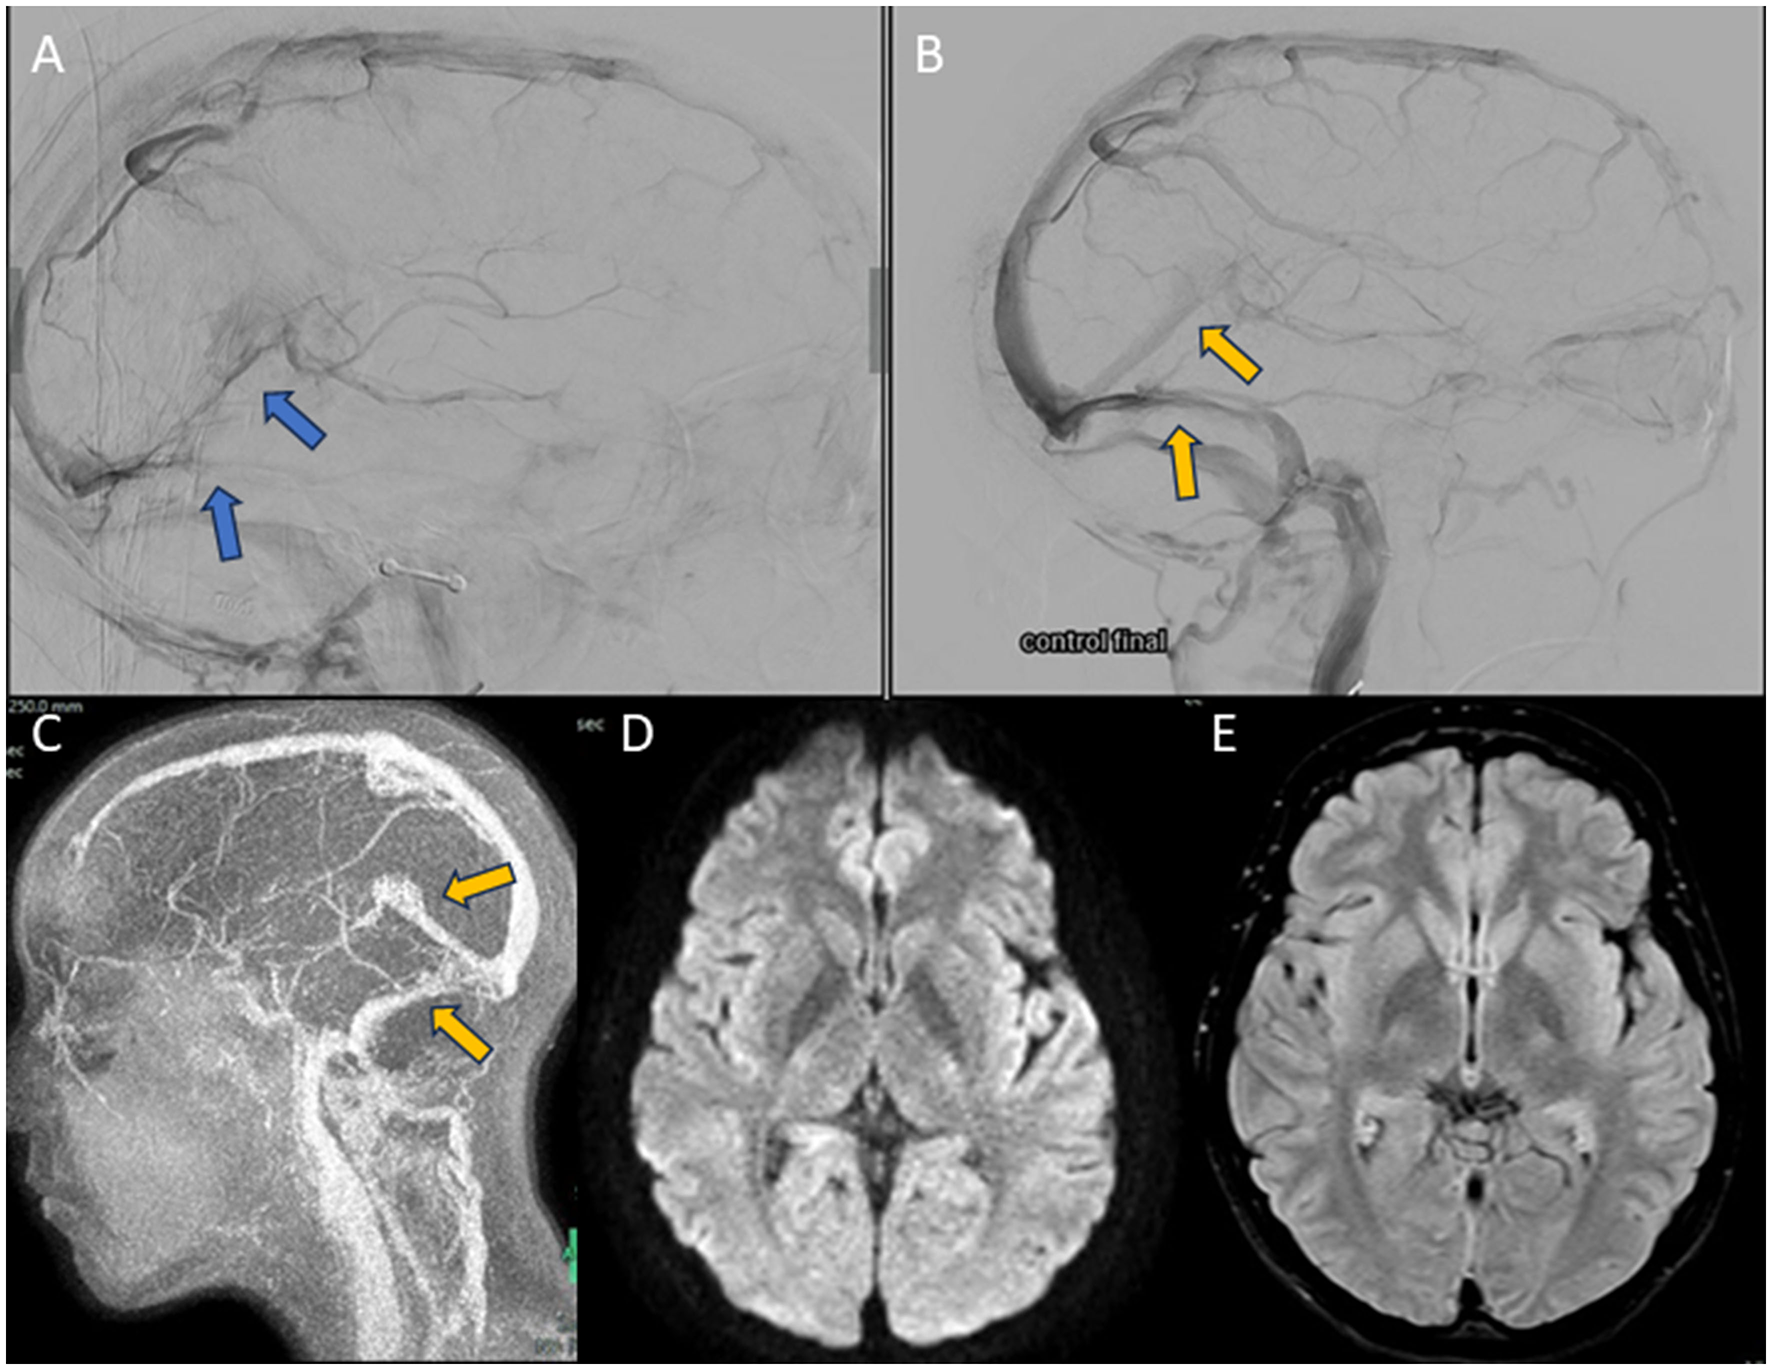

Figure 4. Images obtained during the course of case 2. (A, B) Selective right internal carotid arteriography in venous phase, lateral views. (A) Pre-MT image. Thrombosis of rectus sinus, deep cerebral veins, transverse and sigmoid sinuses (blue arrows) is seen. (B) Post-MT image. Recanalization of the rectus sinus (yellow arrow), torcula, superior sagittal sinus, and both transverse sinuses (yellow arrow) is seen. (C–E) Brain MRI performed 7 days after MT. (C) 2D-TOF MRI angiography, sagittal view. Shows the complete recovery of the venous system (yellow arrow). (D) DWI sequence. No acute ischaemic lesions are evident. (E) FLAIR sequence. No images suggestive of residual ischaemic or haemorrhagic pathology are seen.